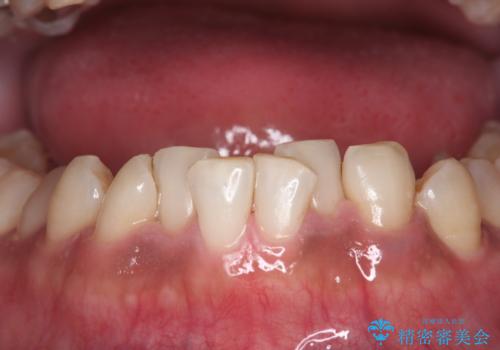

コーヒー、タバコなどで着色した歯をPMTCで、きれいに!!

- 長年の喫煙とコーヒーによる歯の、着色をとりたいと来院されました。

かなり汚れがこびりついていたので、PMTC(歯科医院で行うプロフェッショナルクリーニング)60分コースを

おすすめしました。

PMTC(60分コース) 担当衛生士 進藤

歯の着色だけでなく、汚れもとれ歯の表面がツルツルなって気持ちがいいと

大変満足していただけました。